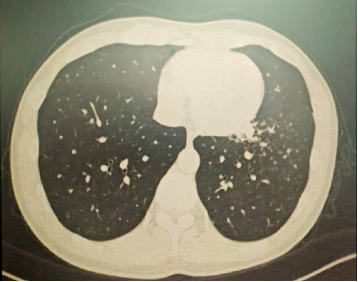

以上是他的胸部CT影像,主要表现为左下肺炎症,片絮影+磨玻璃影。

肺部感染的影像学特征

多发性结节伴快速进展

CT表现为双肺多发实性结节(直径0.5-3cm),结节边缘可见毛刺征及分叶征,特征性表现为短期内体积呈几何级数增长(如1周内增大10倍),需与转移瘤、结核球等鉴别。

混合性密度影与胸腔积液

40%病例出现磨玻璃影与实变影共存,部分结节中央可见液化坏死;30%伴单侧渗出性胸腔积液,积液分析呈渗出性但培养阴性,此表现易误诊为脓胸。